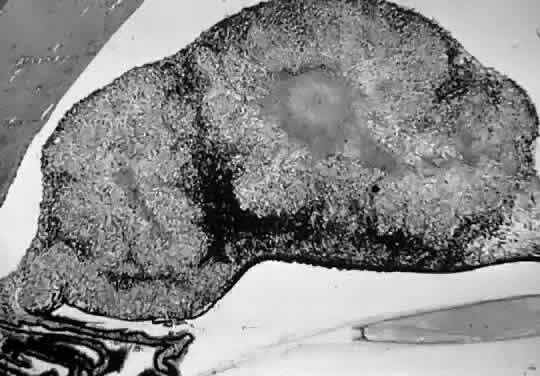

Tubercles are the characteristic lesions of primary tuberculosis. They begin as an acute inflammation marked by accumulation of polymorphonuclear leukocytes. After the development of hypersensitivity, the leukocytes are replaced by lymphocytes and macrophages as a granulomatous reaction develops. Central caseation is surrounded by a ring of epithelioid cells, which may fuse to form multinucleated giant cells (Fig. 1). Peripherally are found lymphocytes, macrophages, and proliferating fibroblasts.

Fig. 1. Tuberculous iris mass with caseating granuloma (hematoxylin and eosin, × 110). (Dunn JP, Helm CJ, Davidson PT: Tuberculosis. In Pepose JS, Holland GN, Wilhelmus KR [eds]: Ocular Infection and Immunity, p 1413. St Louis, Mosby-Year Book, 1996.)